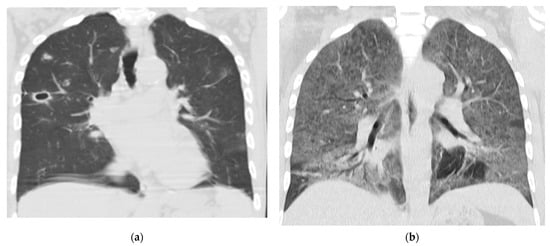

| Pulmonary pattern | Interstitial pattern | 3 (6) | 2 (15) | 3 (75) | 1 (33) |

| Pulmonary nodules | 0 | 11 (85) | 1 (25) | 0 | |